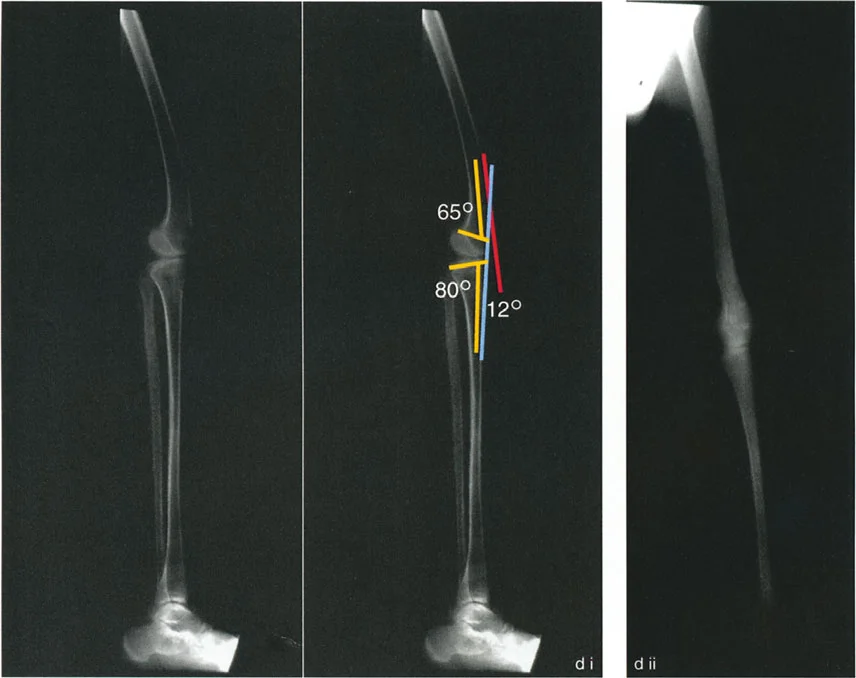

- الأشعة السينية الطويلة للطرف السفلي بالكامل أثناء الوقوف (Standing Long-Leg AP View): تُعد هذه الأشعة حاسمة لتقييم المحاذاة الميكانيكية للطرف السفلي بأكمله. تُظهر بدقة درجة الانحراف الأفحج (Varus) أو الأروح (Valgus) وتساعد في تحديد مركز دوران التشوه (CORA).

- الأشعة الجانبية الطويلة للطرف السفلي بالكامل أثناء الوقوف في أقصى بسط (Standing Long-Leg Lateral View in Maximum Extension): تُستخدم لتقييم تحدد حركة الركبة (FFD) والركبة الارتدادية (Recurvatum)، وتحديد ما إذا كان التشوه عظميًا أو ناتجًا عن تقلص في الأنسجة الرخوة.

تتضمن جراحة قطع العظم قطع العظم (عادة عظم الفخذ أو الساق) وإعادة تشكيله لتغيير محاذاة المفصل. يمكن أن يكون القطع:

- قطع العظم بالوتد المفتوح (Opening Wedge Osteotomy): يتم عمل قطع في العظم ثم فتح فجوة صغيرة تُملأ غالبًا بطعم عظمي، مما يطيل الجزء المعني من العظم ويصحح المحاذاة.

- قطع العظم بالوتد المغلق (Closing Wedge Osteotomy): يتم إزالة جزء صغير من العظم على شكل وتد، ثم تُغلق الفجوة وتُثبت العظام، مما يقصر الجزء المعني ويصحح المحاذاة.

يتم تثبيت العظام بعد القطع باستخدام صفائح ومسامير أو تثبيت خارجي، لضمان التئام العظم في الوضعية الجديدة.

تصحيح تحدد حركة الركبة (Flexion Deformity - FFD)

تحدُّد حركة الركبة هو عدم القدرة على مد الركبة بالكامل. يمكن أن يكون سببه عظميًا أو ناتجًا عن تقلص في الأنسجة الرخوة.

- التشخيص الدقيق: يجب تحديد ما إذا كان تحدد الحركة ناتجًا عن تشوه عظمي (تقوس أمامي في الفخذ أو الساق) أو تقلص في الأنسجة الرخوة (الأوتار الخلفية، محفظة المفصل).

- قطع العظم التمديدي (Extension Osteotomy):

- إذا كان التشوه عظميًا، يتم إجراء قطع عظم تمديدي في عظم الفخذ أو الساق لتصحيح التقوس.

- الأستاذ الدكتور محمد هطيف يؤكد على أهمية عدم تصحيح الساق بأكثر من 90 درجة PPTA لتجنب فقدان الميل الخلفي الطبيعي للساق.